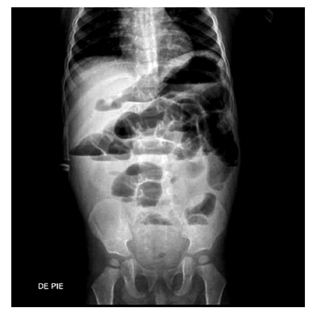

Varón de 10 meses que ingresa a emergencia pediátrica con historia de vómitos y distensión abdominal de 2 días de evolución. La radiografía de abdomen mostró una dilatación intestinal y niveles hidroaéreos (Figura 2). Con el diagnóstico de obstrucción intestinal ingresa a la sala de operaciones donde se evidencia una invaginación intestinal, teniendo al divertículo de Meckel como cabeza de invaginación. Se procede a desinvaginación manual, resección de segmento intestinal que contiene al divertículo y anastomosis término-terminal. La evolución posoperatoria fue favorable.